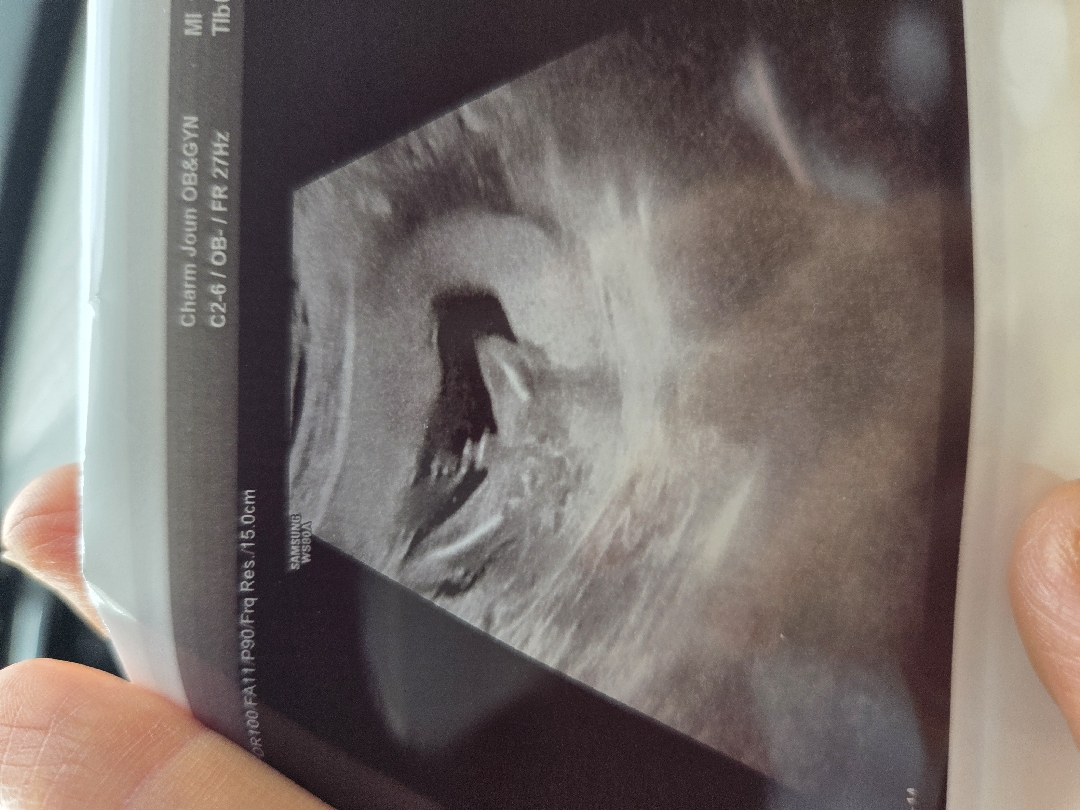

첫째(아들) 때랑 너무 다른 임신 증상 때문에 딸일까 하고 내심기대 했는데, 오늘 🌶존재감을 확실해 보여주는 아들입니다~ 든든한 아들 둘 엄마가 되었네요 ㅎㅎ 아들이라하니 친정엄마(딸3, 아들1) 왈 "남들 있는거 너도 다 있어야지, 셋째 가자!!" 아니,, 친정엄마 맞냐고 ㅜㅠ

다리사이 뿅! 귀엽네요 축하드려요